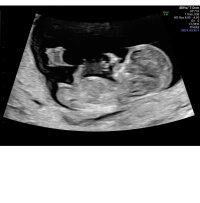

13mm og tilbake igjen til 8+2hematomet kan ses under og mot høyre av fostersekken, og har endret seg veldig, så dette ser lovende ut